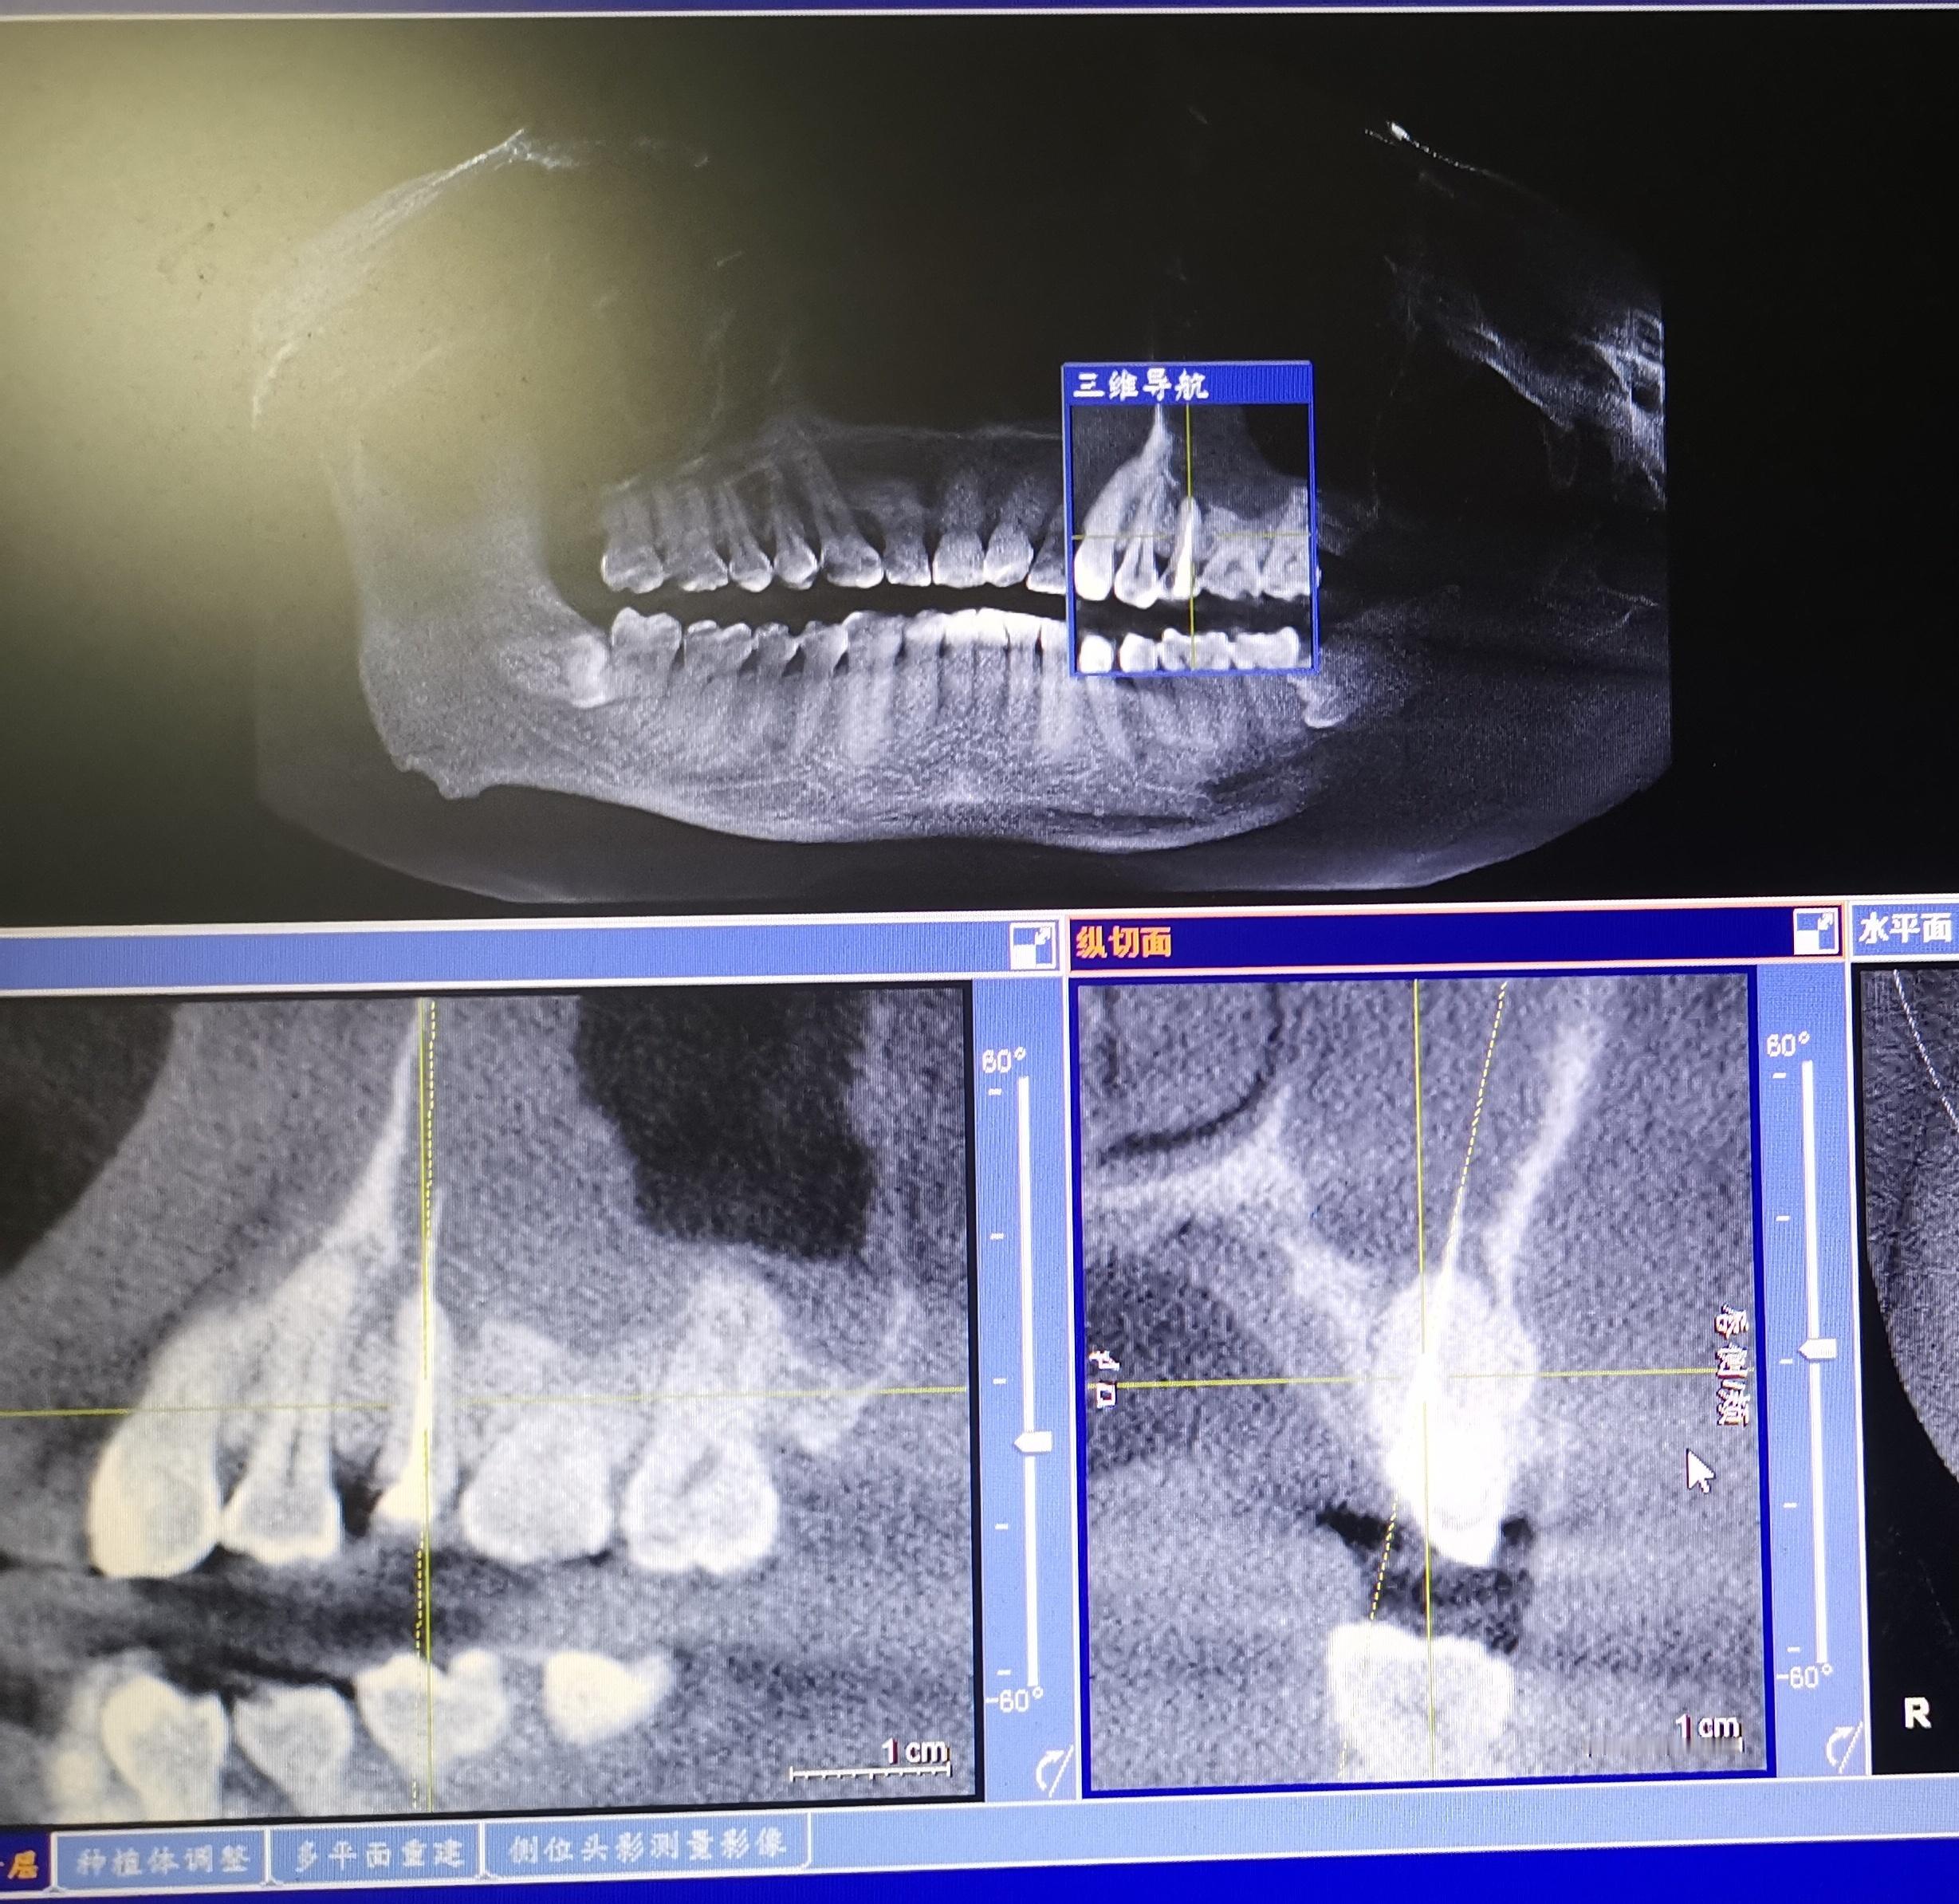

接一例转诊,急性上颌窦炎,发热。 两个月前在一诊所做过根管治疗。我问,当时医生拍片后没说什么吗?答,直到整个疗程结束一直没拍过片子。嘱抗生素用几天,再来掏一下试试。大家猜是啥?